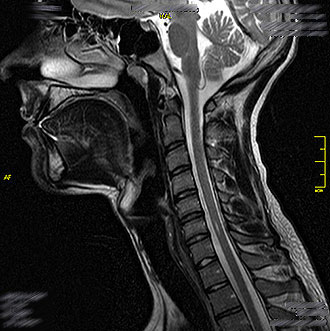

Die MRT Hals ist eine besonders wichtige Untersuchung in der Kopf-Hals-Diagnostik. Im Kernspin Zentrum Köln wird sie eingesetzt, um die Strukturen des Kehlkopfs, der Speicheldrüsen, der Lymphknoten sowie den Nasen-, Mund- und Rachenraum detailliert darzustellen.

Dank moderner Magnetresonanztomographie (MRT) lassen sich Entzündungen, Tumoren oder funktionelle Veränderungen frühzeitig und strahlungsfrei erkennen.

Die MRT des Kehlkopfs (Larynx) ermöglicht eine genaue Beurteilung der Stimmbänder, der Kehlkopfmuskulatur und der umliegenden Weichteile. Im Kernspin Zentrum Köln wird sie häufig bei Stimmstörungen, anhaltender Heiserkeit oder Schluckbeschwerden durchgeführt.

Mit dieser Untersuchung können Kehlkopfentzündungen ebenso erkannt werden wie gutartige oder bösartige Veränderungen – etwa ein Kehlkopfkarzinom. Durch die hochauflösende Darstellung wird die MRT auch zur Therapiekontrolle nach Operationen oder Bestrahlungen eingesetzt.

Die MRT des Nasen-, Mund- und Rachenraums (Nasopharynx, Oropharynx, Hypopharynx) spielt eine zentrale Rolle bei der Diagnose von Karzinomen, Entzündungen oder Lymphknotenveränderungen im Halsbereich.

Im Kernspin Zentrum Köln wird diese Untersuchung eingesetzt, um unklare Schluckbeschwerden, chronische Infektionen oder Raumforderungen abzuklären. Besonders bei Lymphknotenvergrößerungen kann die MRT helfen, zwischen entzündlichen und tumorbedingten Veränderungen zu unterscheiden.

Die MRT Hals im Kernspin Zentrum Köln ermöglicht eine exakte und umfassende Diagnostik sämtlicher Strukturen im Halsbereich – vom Kehlkopf über die Speicheldrüsen bis hin zum Rachenraum. Sie bietet die beste Grundlage, um Ursachen von Heiserkeit, Schluckbeschwerden, Schwellungen oder Entzündungen sicher zu erkennen und gezielt zu behandeln.